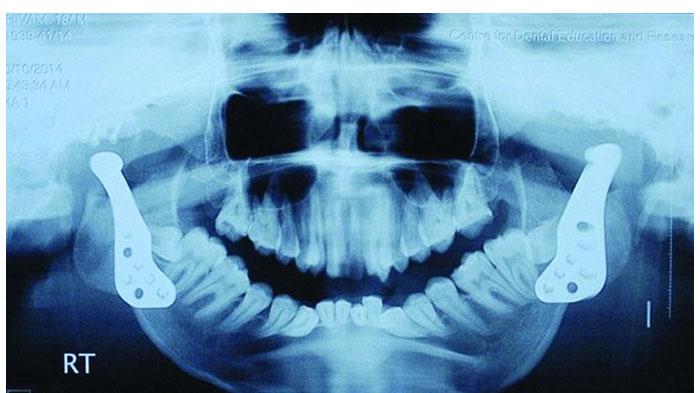

تمكن شاب هندي(19 عاما) من فتح فمه لأول مرة منذ ثماني سنوات بعد تعرضه لإصابة تسببت في التحام فكه الأسفل بقاعدة جمجمته.

ولم يستطع شيفام شارما، وهو من بلدة هاثراس بولاية أوتاربراديش، أن يأكل أو يتكلم منذ سقوطه من احد الأسطح، ما أدى أيضا إلى الحد من قدرته على التنفس وخاصة أثناء النوم. غير أن طبيبين هنديين تمكنا من إعادة بناء فكه باستخدام مفصلين صناعيين، ما مكنه من تحريك فمه بصورة كاملة.

ويشير الطبيب اجوي رويشودري وزميلته انجكيلا بوتيا، اللذين أجريا الجراحة البالغة التعقيد بمعهد عموم الهند للعلوم الطبية في نيودلهي، إلى أن العملية التي أجرياها تعد الأولى من نوعها بالهند.

ويقول الطبيب رويشودري إن الحالة المرضية التي أصابت شيفان يمكن أن تحدث نتيجة للسقوط أو التهاب الأذن. ويعتبر مفصل الفك حيث يلتقي الفك الأسفل بالجمجمة المفصل الأكثر تعقيدا في جسم الإنسان، و بات في وسع شيفان حاليا أن يفتح فمه ويتحدث ويأكل بصورة طبيعية.